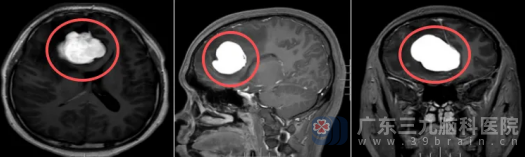

我院影像检查提示,在患者右侧额部大脑镰旁,一个大小约47mm×40mm×44mm的肿瘤清晰可见,堪比一个鸽子蛋。

“肿瘤的位置非常关键,”神经外十科欧阳辉教授解释道,肿瘤正好压迫到与视觉息息相关的右侧视神经,这是导致右眼中心视力模糊的直接原因。

神经外十科团队组织了多学科讨论,从影像特征看,虽然首先考虑常见的脑膜瘤,但也需要警惕孤立性纤维性肿瘤等其他可能。无论病理类型如何,这个位置的肿瘤都如同“不定时炸弹”,必须尽快手术。

术前影像

神经外十科团队通过显微外科技术,小心翼翼地分离肿瘤与正常脑组织的边界。术中发现肿瘤与大脑镰及重要静脉窦关系密切,血供丰富,每一步操作都要求极高的精准度。手术持续了7个小时,肿瘤被完整切除,并且保护了脑组织和视神经。